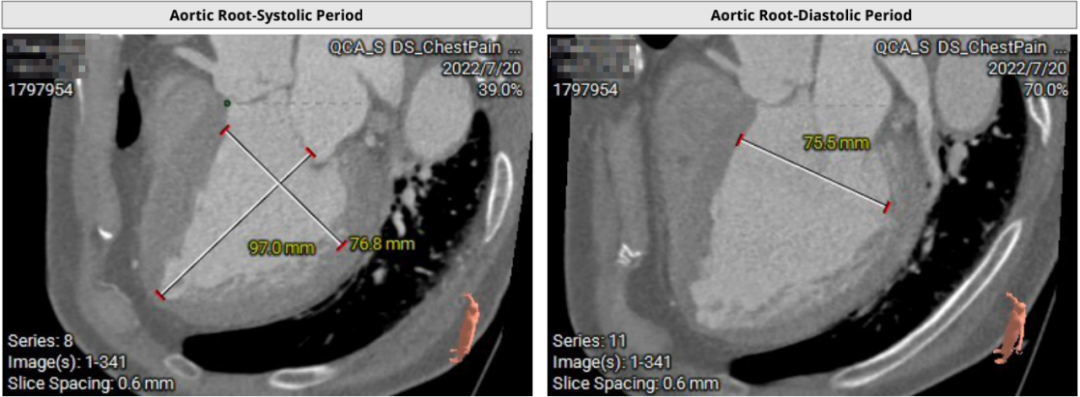

患者64岁男性,Type 0 型二叶瓣、横位心。主动脉瓣中度狭窄,重度反流,瓣环周长92.0mm,平均径29.0mm。LVOT周长98.7mm,升主扩张,窦部结构极限,锚定能力极限。入路两侧血管轻度迂曲,分叉高度可,两侧血管内径均>8mm。